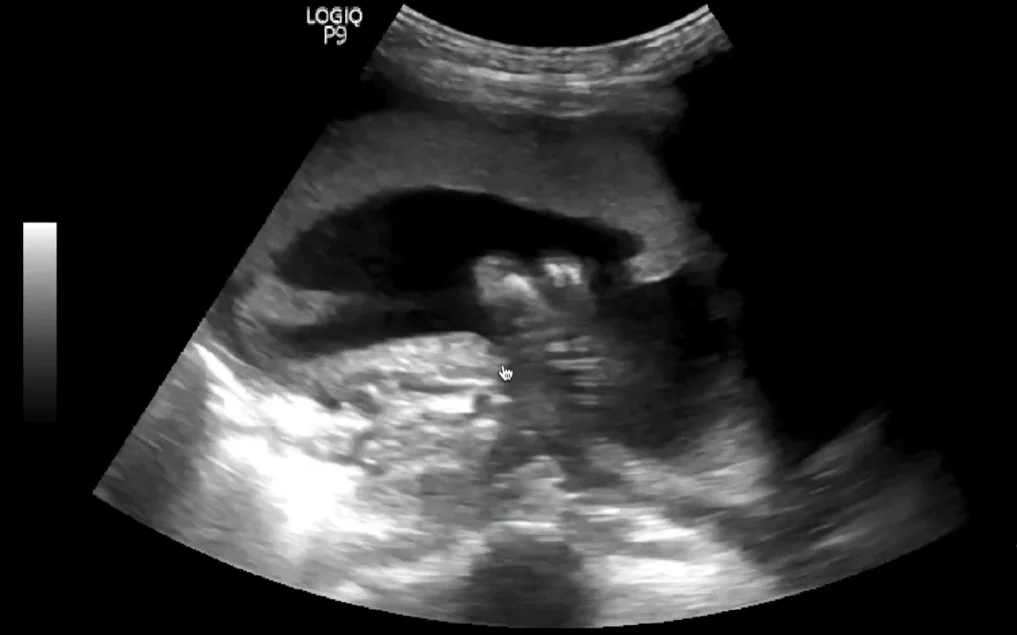

Giãn tĩnh mạch rốn thai nhi (Umbilical Vein Varix - UVV)